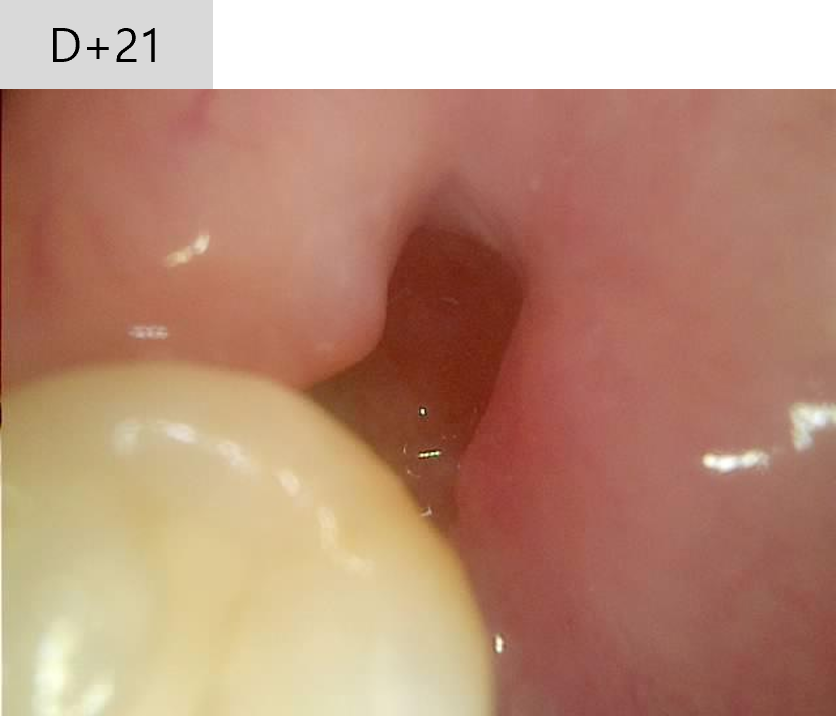

발치 후 21일 째

- "많이 좋아졌어요"

발치 후 21일, 발치 부위의 노출된 잇몸뼈는 잇몸으로 완전히 덮임. 드라이 소켓 치유.

- 처치 : 정상적인 발치와 소견. 마지막 드레싱 시행하고, 3일 처방 시행.